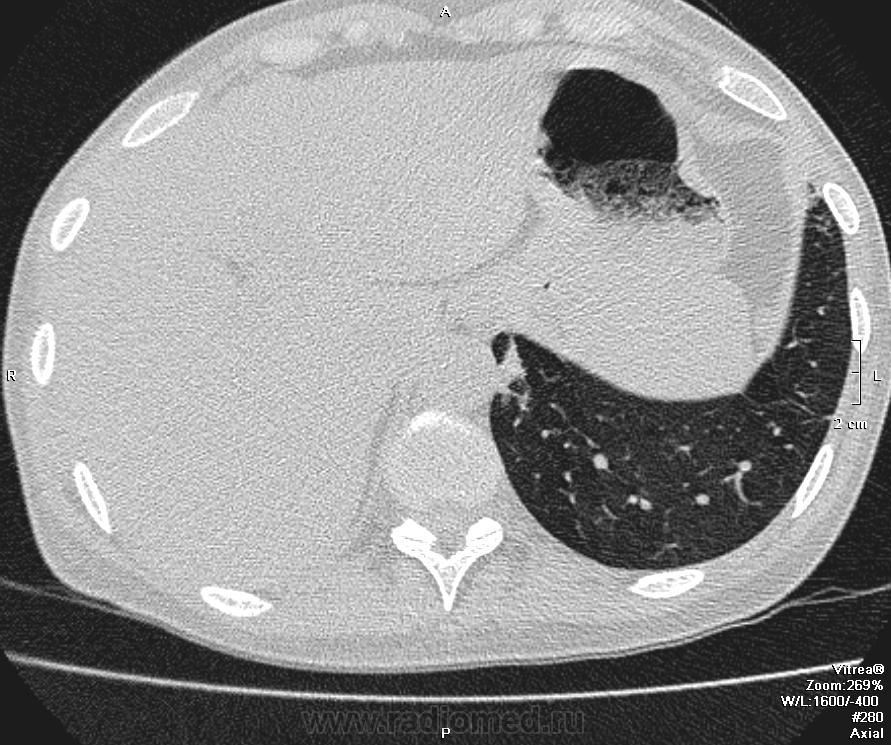

Как и обещала публикую КТ ОГК.

Итог- tbc цирротическая форма, очаги отсева в обоих легких (больше справа). много очагов Гона. Деструкции не выявлено, как и плеврита справа. Плевродиафоагмальные спайки (уже даже шварты).

Все что казалось деструкцией - оказалось тракционными цилиндрическими и мешотчатыми бронхоэтазами.

Тракционные бронхоэктазы типичны для цирротической формы. У Тюрина подробно это описано.

Множество отсевов и очаги Гона везде, кальцинаты во ВГЛУ говорят за совсем не свежий специфический туберкулезный процесс.

много отсевов, больше в шестерке и очаги Гона. Относительно нижней доли справа ей повезло больше.